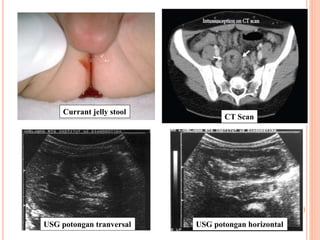

USG potongan tranversal USG potongan horizontal

CT Scan

Currant jelly stool

10 USG potongan tranversalUSG potongan horizontal CT Scan Currant jelly stool